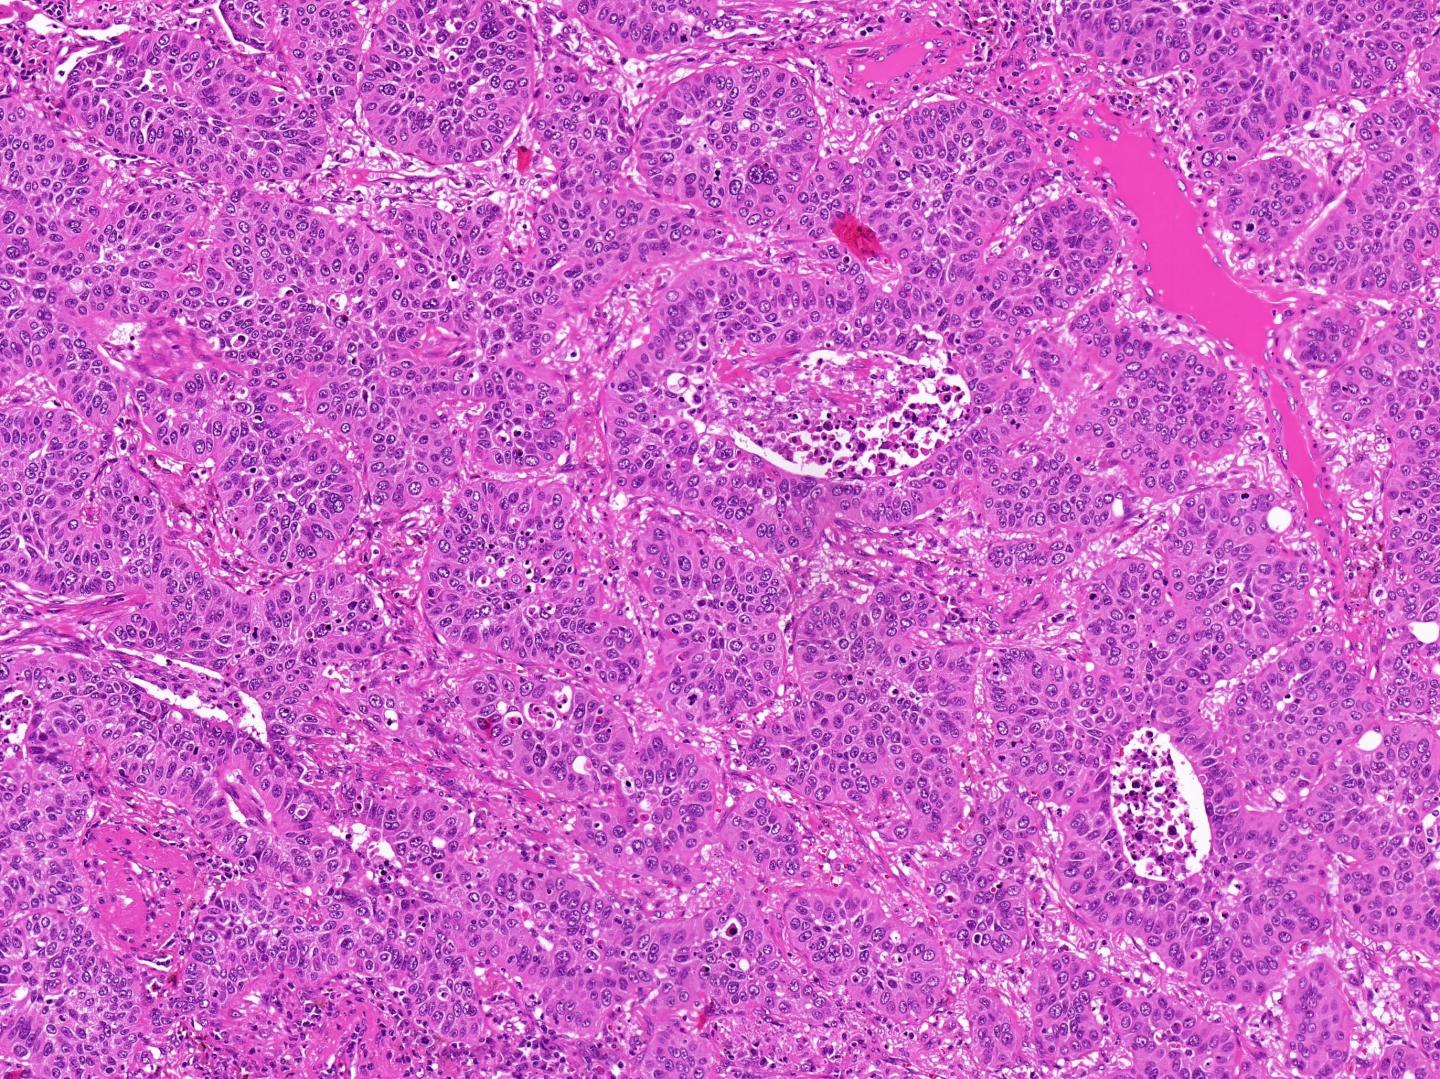

image: Under the microscope, both squamous cell carcinoma of the lung and squamous cell carcinoma of the head and neck appear as dense cell groups with non-specific growth patterns, making them impossible to distinguish based on tissue microstructure.

When trying to distinguish between metastases and a second primary tumor, pathologists will usually use established techniques such as analyzing the cancer's microstructure and detecting characteristic proteins in the tissue. However, due to the marked similarities between head and neck cancers and lung cancers in this regard, these tests are usually inconclusive. "In order to solve this problem, we tested tissue samples for a specific chemical alteration known as DNA methylation," explains Prof. Capper who, like Prof. Klauschen, is a Scientific Member of the DKTK in Berlin. He adds: "We know from earlier studies that DNA methylation patterns in cancer cells are highly dependent on the organ in which the cancer originated."